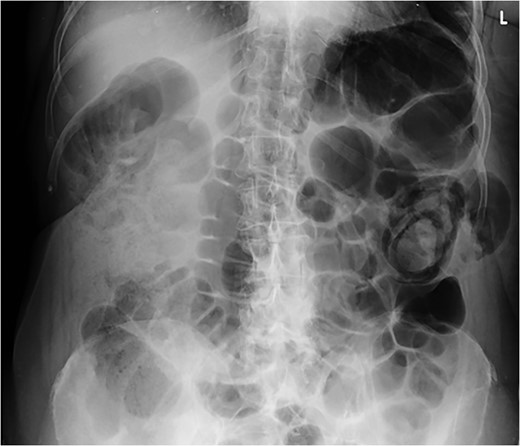

A 72-year-old woman presented with acute lower abdominal pain and nausea. She had not opened her bowels in 5 days and was passing no flatus. Her medical background included Parkinson’s Disease, hypothyroidism, hypertension, pulmonary embolism and deep vein thrombosis. Further history revealed a longstanding swelling in her left flank, diagnosed as a lipoma and excised 15 years ago under local anaesthetic. Interestingly, according to the patient, her swelling was unchanged after the procedure. A community ultrasound done over a year before her acute presentation had suggested the presence of a hernia (Fig. 1); however, the sonographer was not a musculoskeletal specialist and could not confirm the diagnosis. Biopsy only showed subcutaneous fatty tissue and the lump was diagnosed as a recurrent lipoma.

Ultrasound scan of the left flank showing possible hernia in a 72-year-old woman presenting with a flank swelling (dashed line).